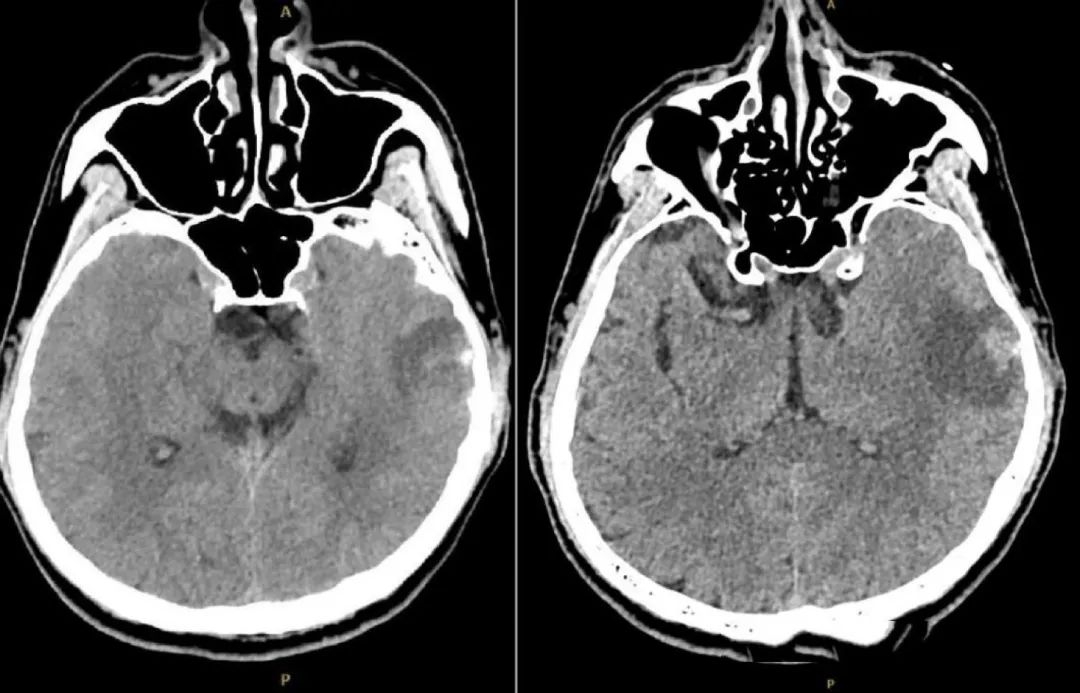

经检查,刘同学的大脑状态在短时间内急剧恶化,多处脑出血和肿胀、头颅CT血管影像中很多静脉血管消失。

图1. 头颅CT(发病后1周):左侧颞叶血肿可能。

图2.左图示左静脉窦及颈静脉均无血流;

右图示深部静脉系统无血流(→)。